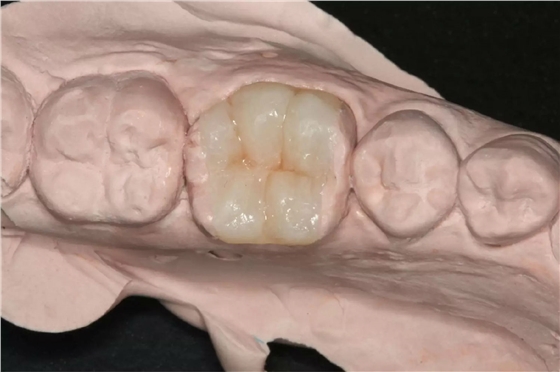

以上為術(shù)中所拔出患牙及剝離的頜骨囊腫。